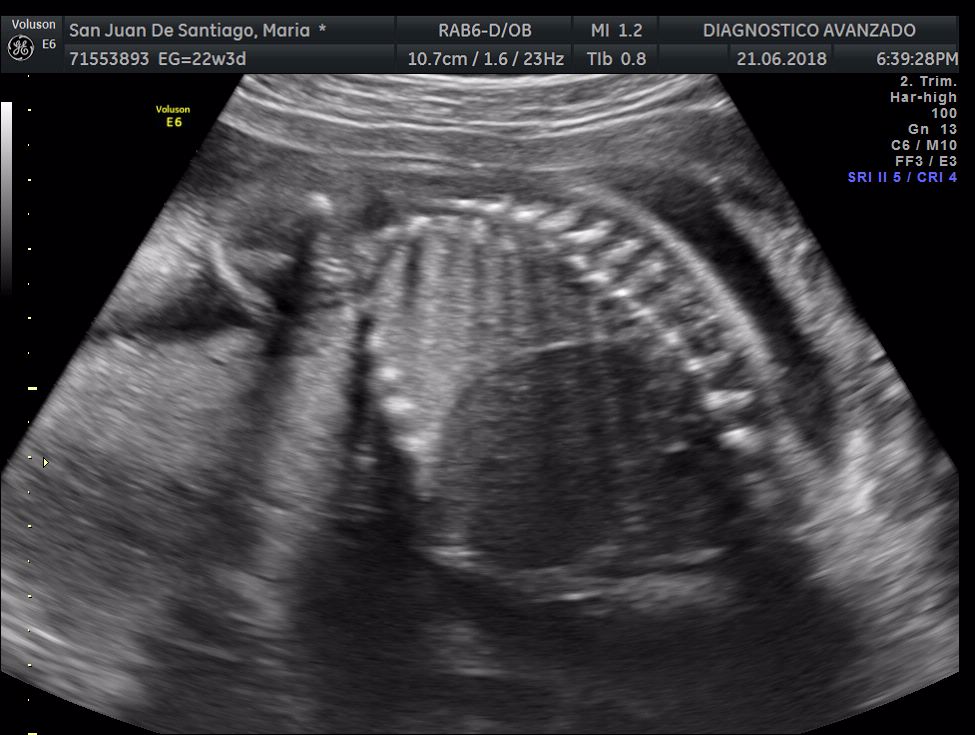

¡Hola a todos! Hoy hemos ido a hacer la tradicional ecografía 3D de la niña, os dejamos todo el material (aunque es un poco demasiado).